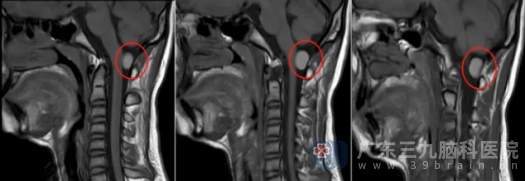

我院神经外十科欧阳辉教授接诊后,为患儿完善相关检查。MR检查给出了更精准的诊断:患儿延髓颈髓交界区后方枕大孔-颈1椎管内存在一个大小约15.7mm×10mm的异常信号,考虑为皮样囊肿或表皮样囊肿,时刻威胁着患儿的健康。

术前影像检查

术后MR检查显示,原延髓颈髓交界区后方椎管内病变已成功切除。病理结果提示为符合神经管原肠囊肿(肠源性囊肿)。出院时,罗昊神志清醒,对答如流,四肢肌力恢复如初。

术后复查影像